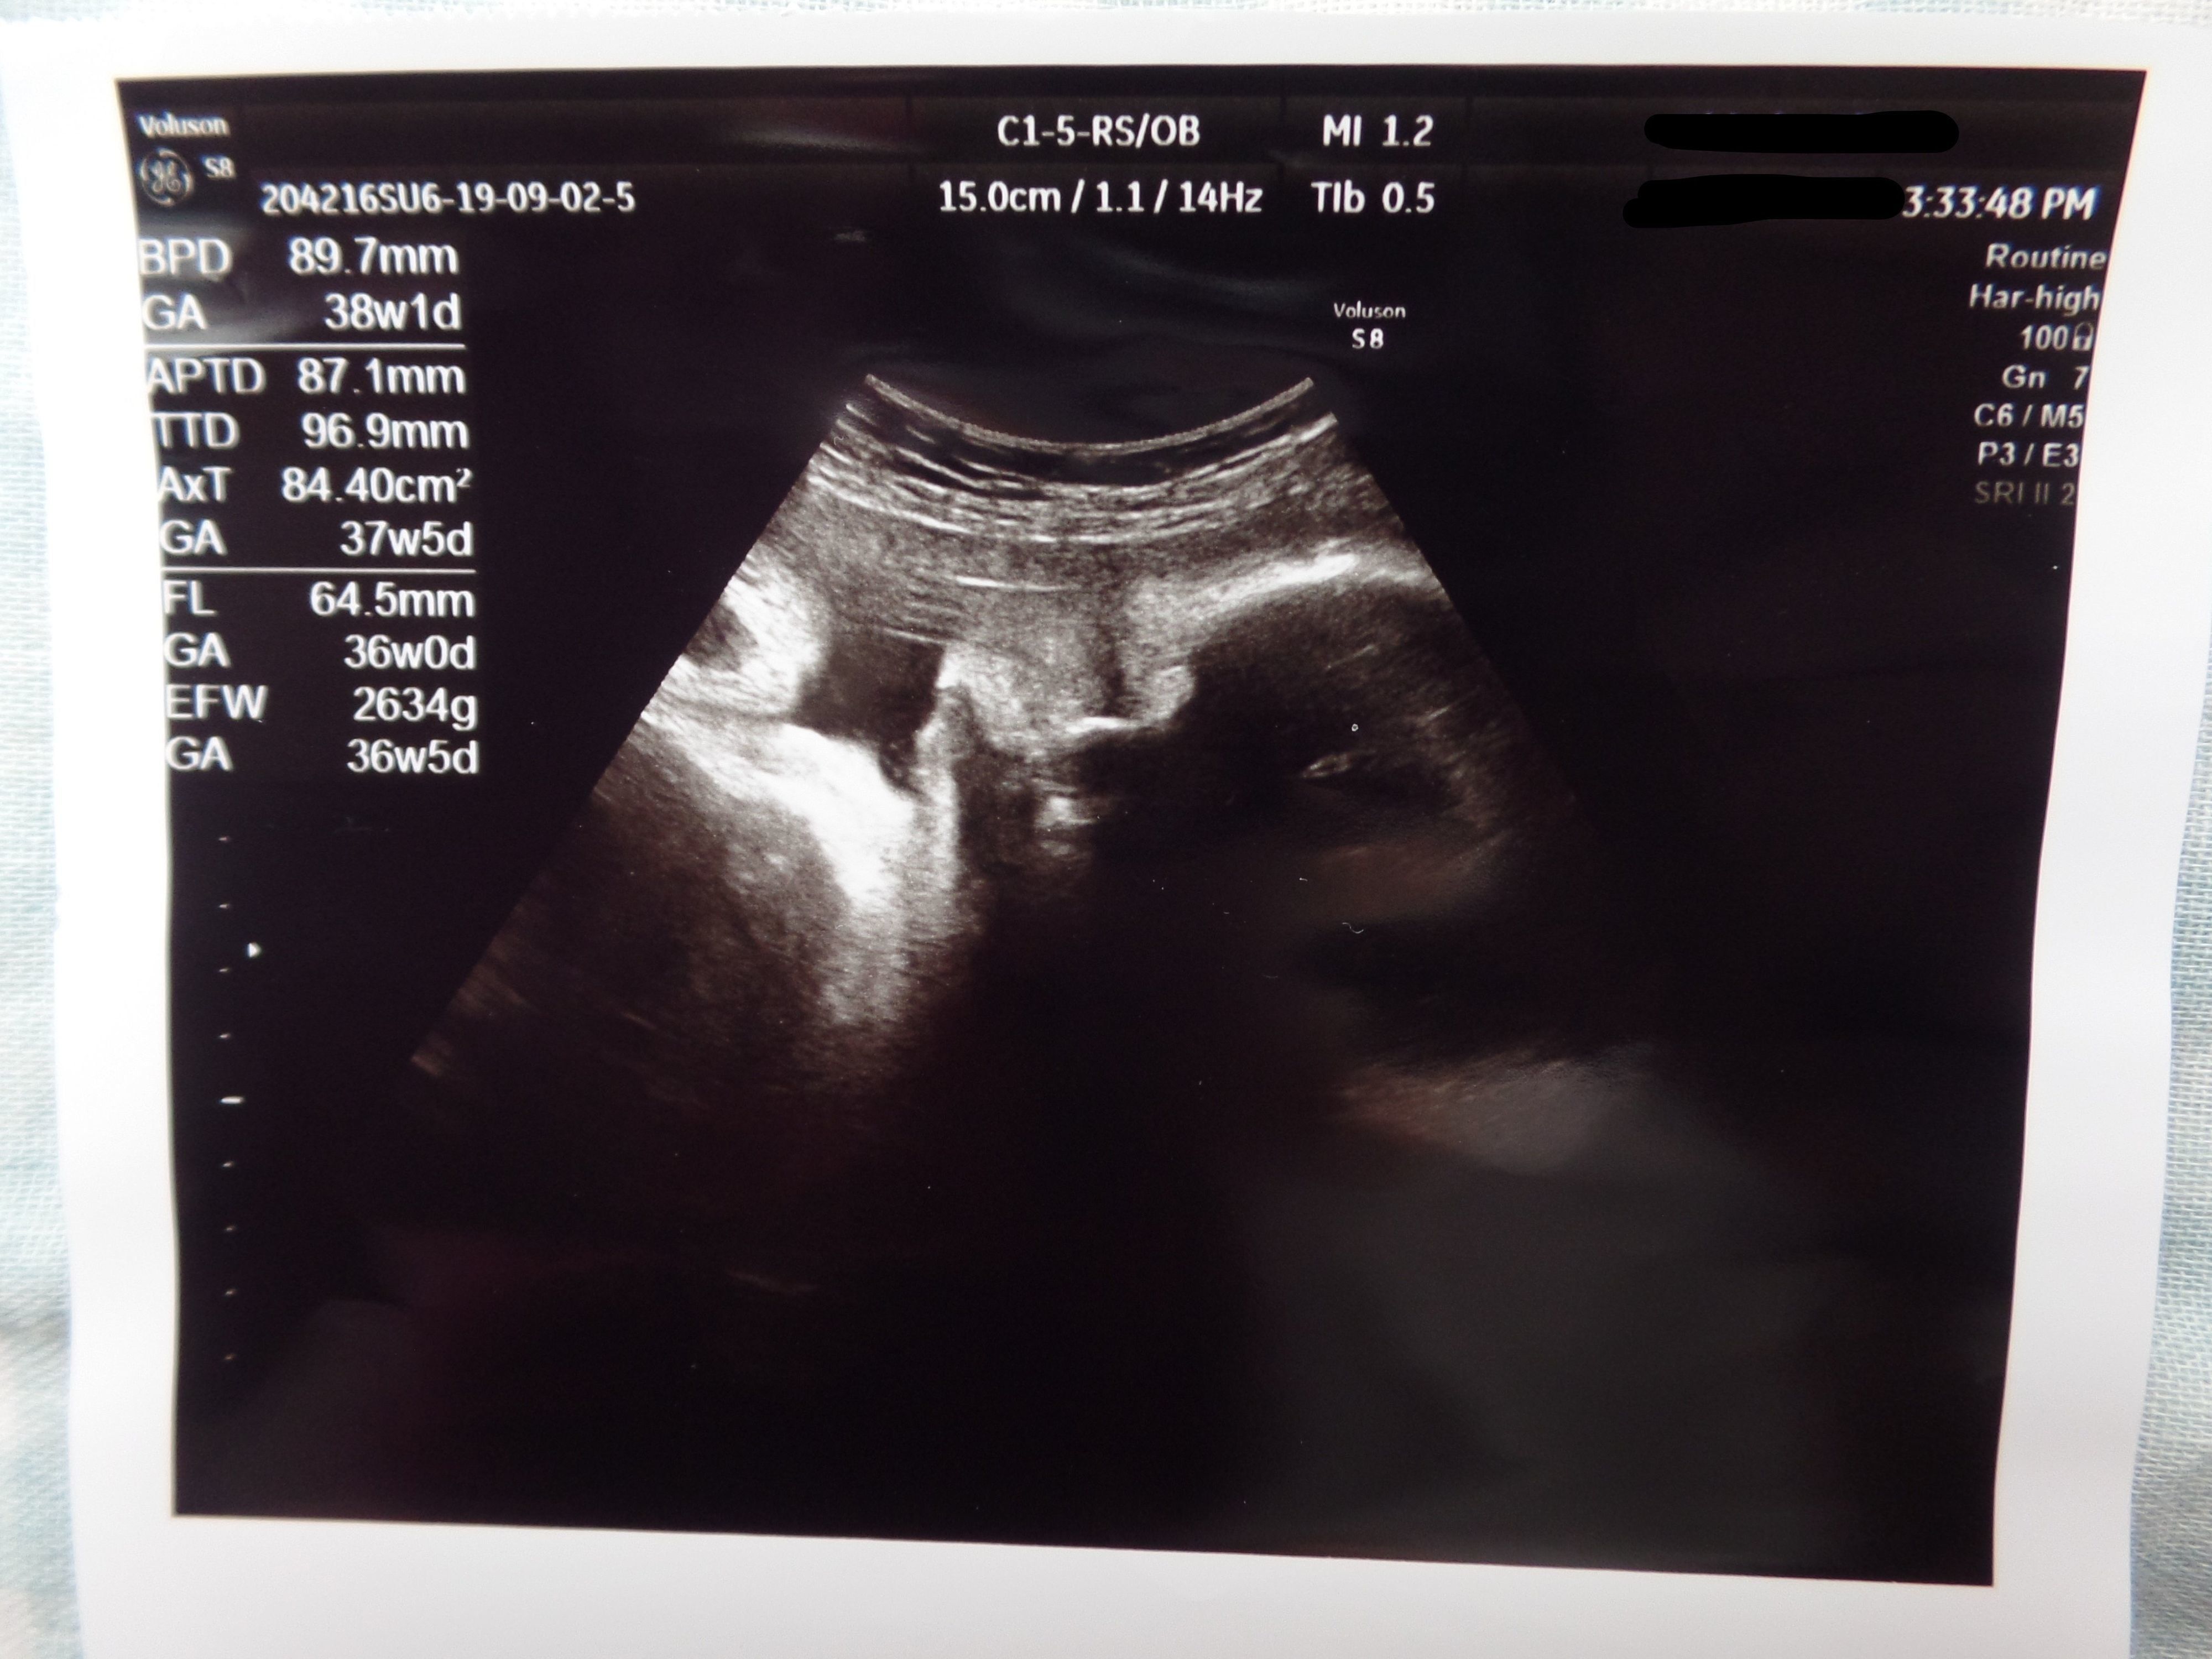

3. 多嚢胞性卵巣症候群(PCOS)から不妊治療を経て高齢出産! エコー写真で喜びを振り返る